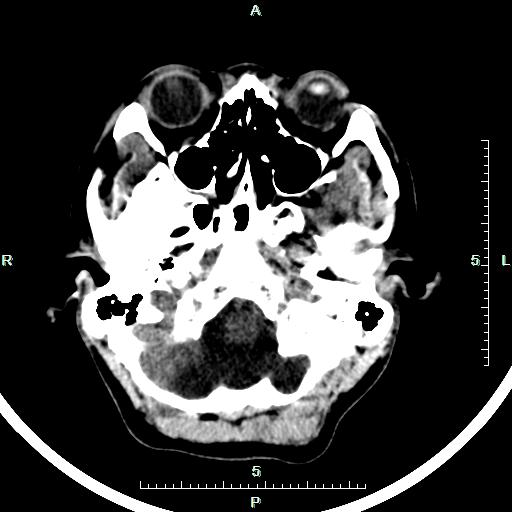

CT50898:男,21岁,先天畸形。

男,21岁,精神病人。 1、巨大枕大池? 2、枕大池囊肿? 3、Dandg-Walker综合征?

考虑Dandy-Walker变异。

枕大池呈囊状扩大,小脑及四脑室未见明显异常,考虑大枕大池。

第四脑室与枕大池相通,小脑半球受压,第四脑室上部相对正常,小脑蚓部相对正常,无脑积水,又为精神病人,可能智能低下。支持考虑Dandy-walkevr综合征(变异型)。

鉴别:1、枕大池囊肿:四脑室前移,病变以上脑室扩大。2、巨大枕大池:形状多为梯形,由中线向小脑表面延伸,内板常有局限压迹,囊肿可与四脑室相通,但四脑室形态位置正常,小脑发育基本正常,无受压变形,除枕大池扩大外,无脑室和小脑异常。